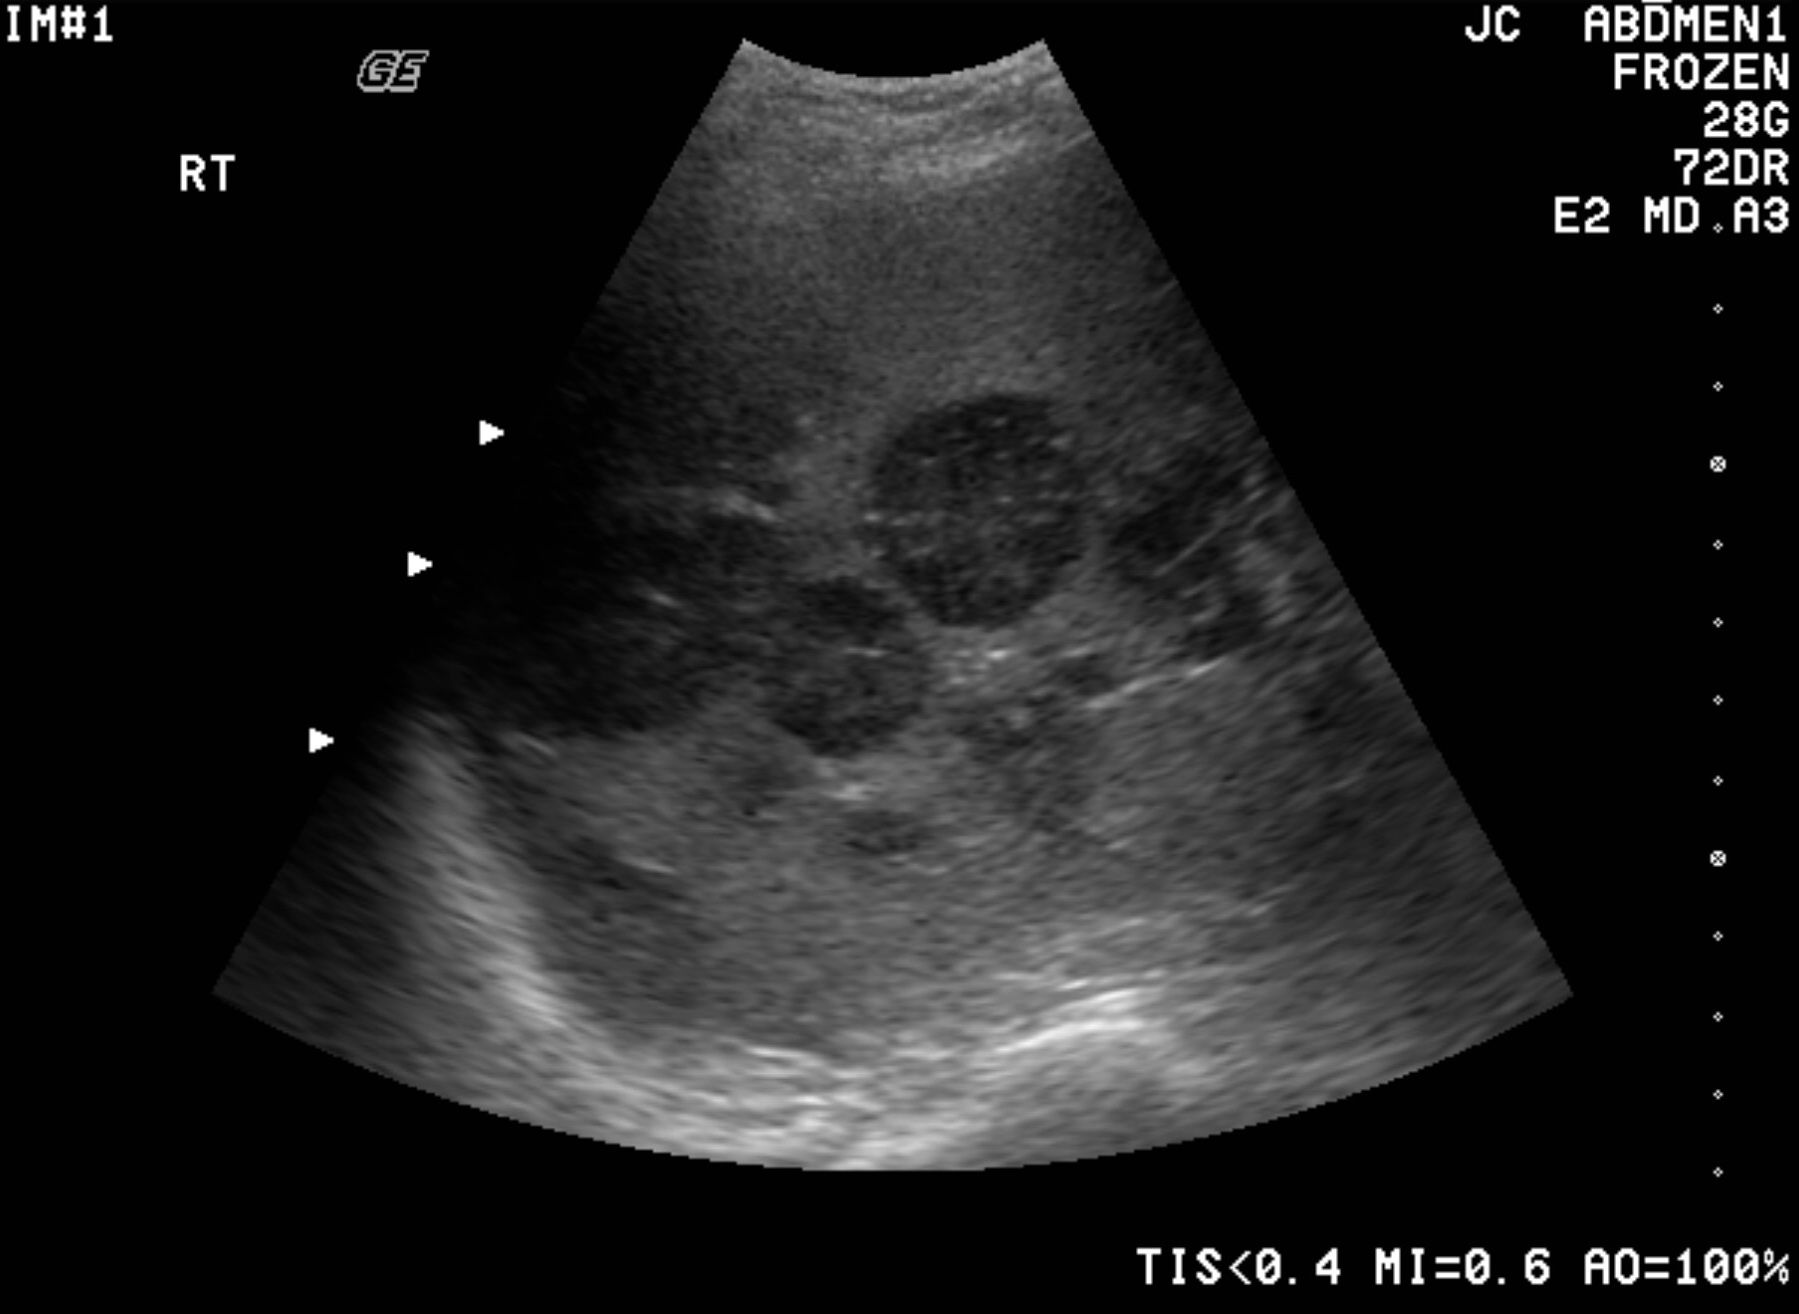

Ультразвуковое исследование (УЗИ) печени с допплерографией является важным методом диагностики заболеваний печени и желчного пузыря. При помощи УЗИ можно получить подробное изображение внутренних органов, определить их размеры, структуру и наличие патологий.

Допплерография — это дополнительный метод УЗИ, который позволяет оценить кровоток в сосудах печени. Этот аспект особенно важен при подозрении на цирроз, гепатит или опухоли печени.

Благодаря допплерографии специалист может выявить нарушения кровотока, определить скорость и направление движения крови в сосудах, что помогает в диагностике различных патологий.